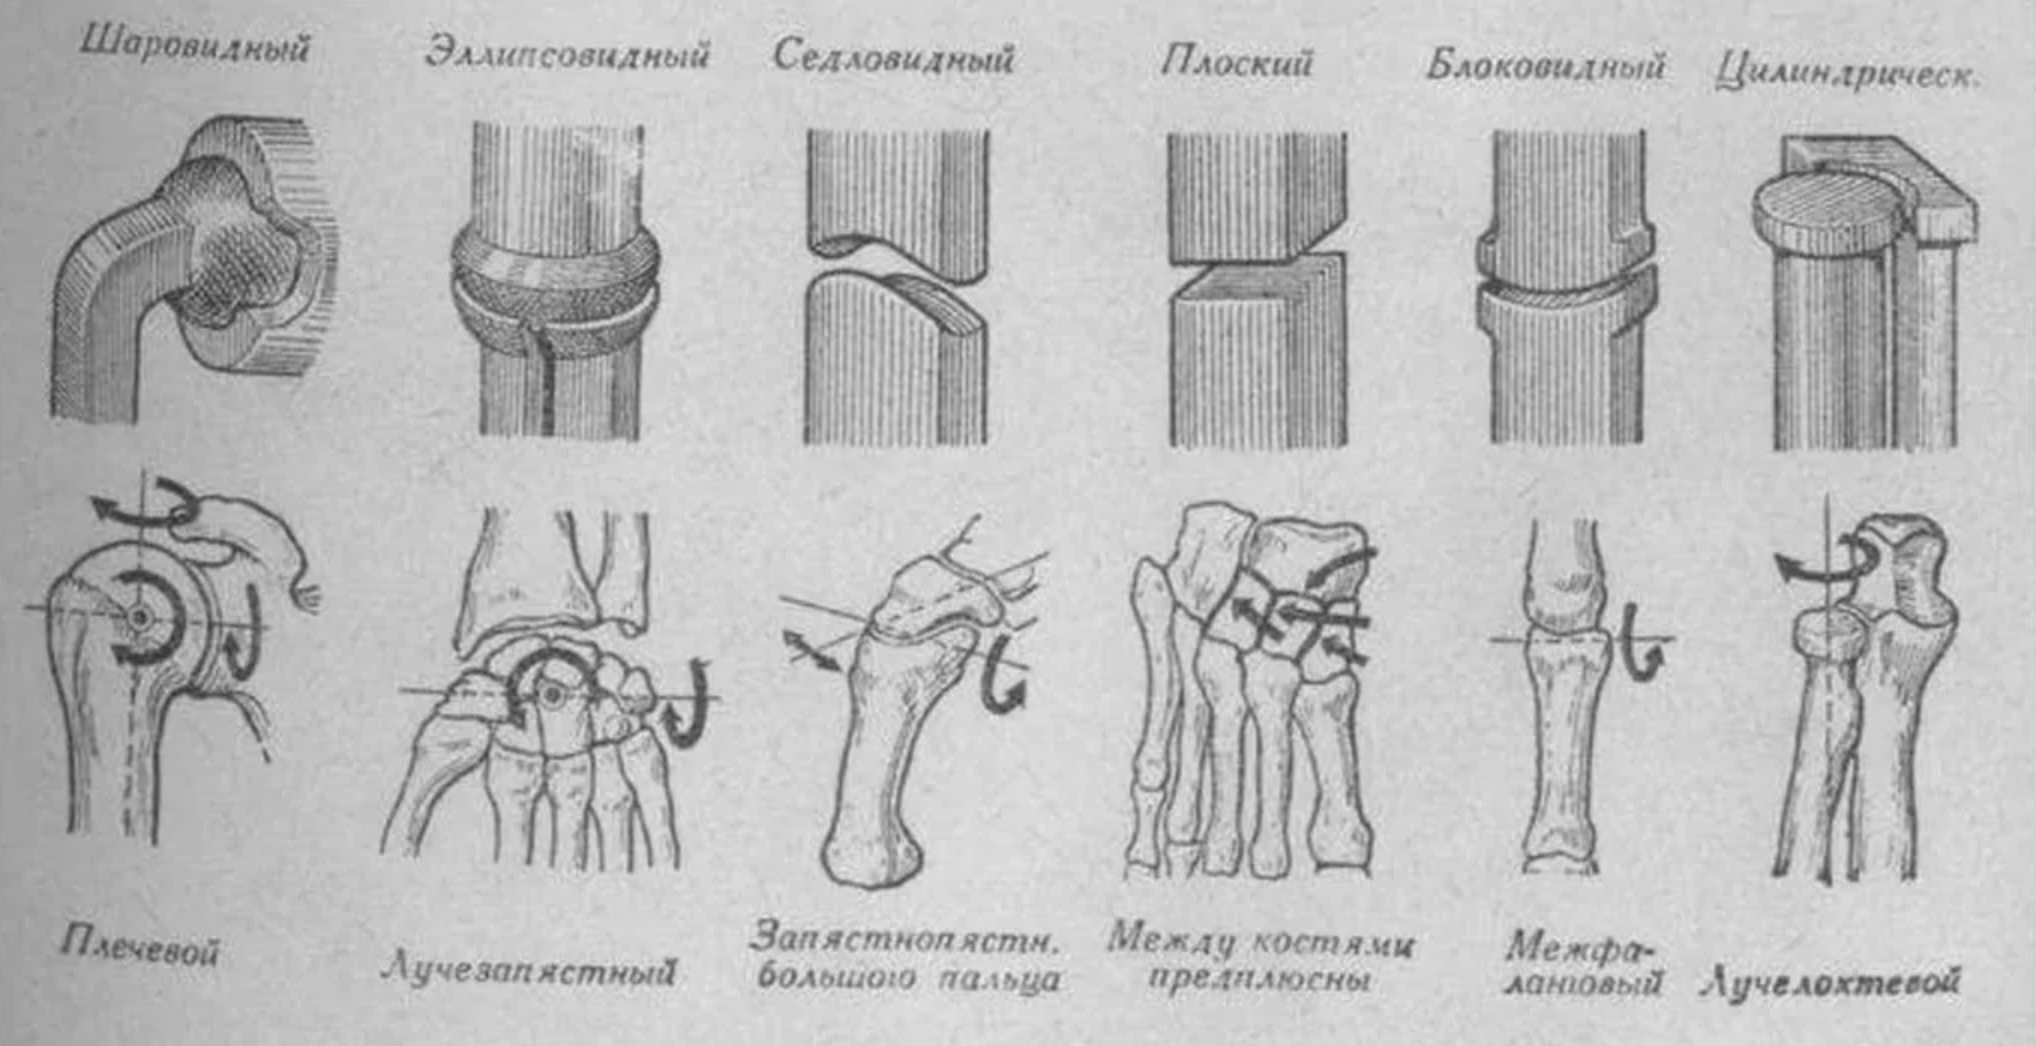

Диаграммы и схемы движения в суставах человека